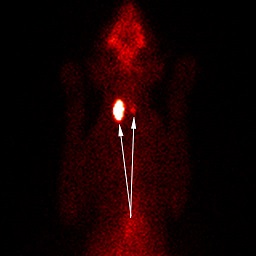

另一個獸醫皮爾森則沒有提出T4檢驗正常範圍值太大的疑慮。不過她有一隻貓是在送去做甲狀腺影像後確診。上面的照片就是皮爾森的貓甲狀腺影像。右邊箭頭指的是正常的甲狀腺,左邊是不正常腫大的甲狀腺。